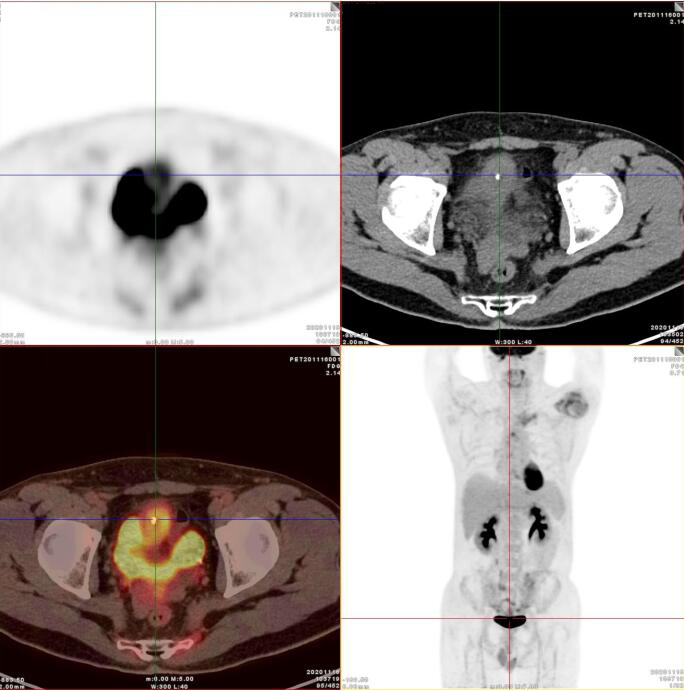

PET/CT影像圖

臍尿管擴(kuò)張,其管壁不均勻增厚,相應(yīng)區(qū)域膀胱頂前壁見一軟組織密度塊影,呈縱向生長(zhǎng),形態(tài)不規(guī)則,大小約3.3x3.8x6.3cm,內(nèi)見斑點(diǎn)鈣化!

膀胱頂前壁軟組織腫塊,放射性攝取SUV Max4.5

膀胱頂前壁軟組織腫塊,放射性攝取SUV Max4.5,延時(shí)4小時(shí)SUV Max8.3

臍尿管區(qū)及膀胱頂前壁軟組織腫塊,代謝增高,考慮臍尿管惡性腫瘤(臍尿管癌),建議穿刺活檢。